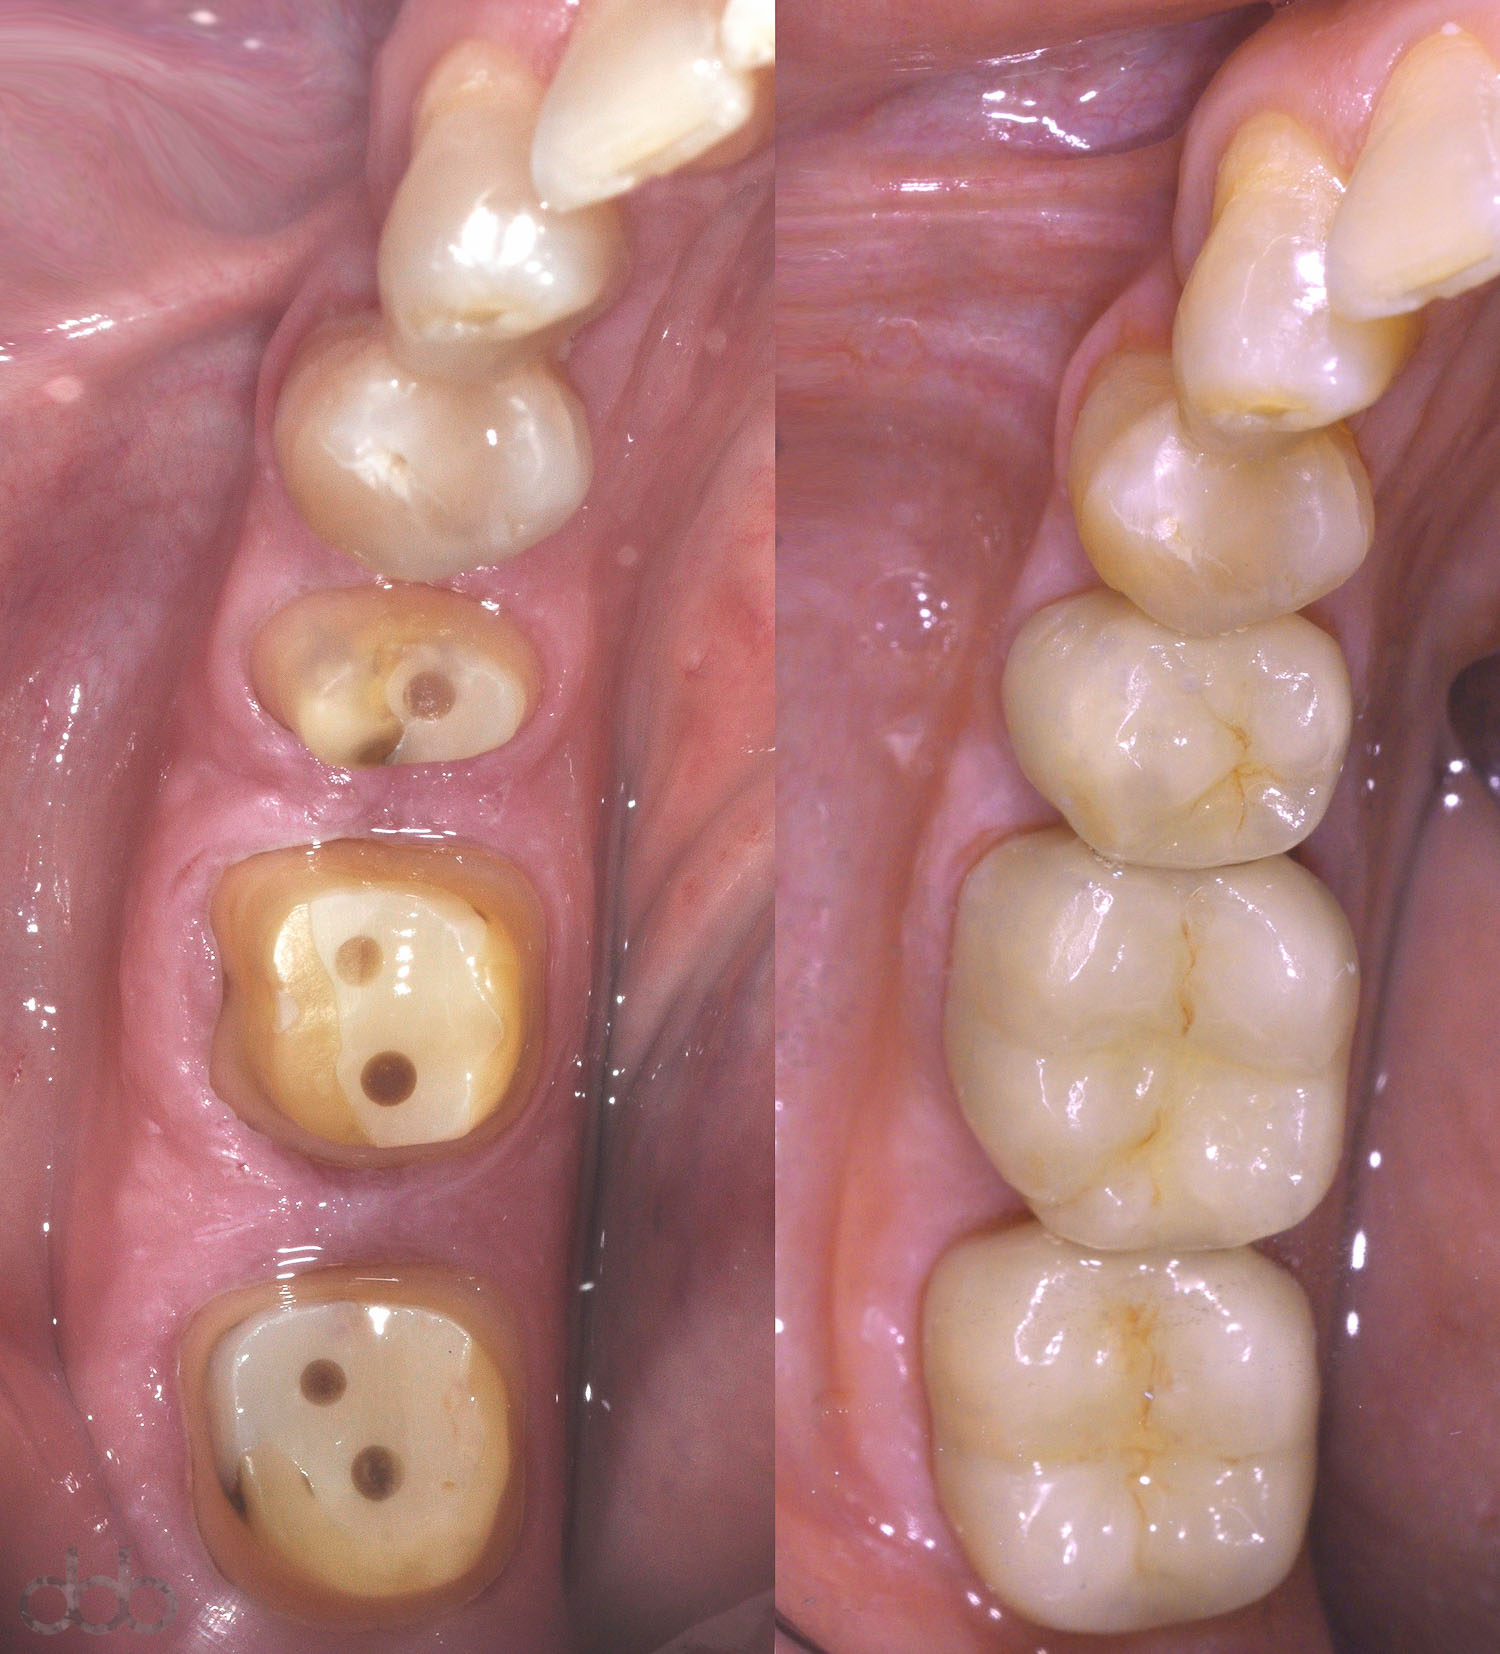

Les couronnes dentaires sont utilisées pour restaurer la partie visible des dents naturelles mais également des implants. Elles peuvent être faites avec différents matériaux tels que le métal, la céramique ou la résine (composite), parfois combinés.

Aujourd’hui pour des raisons esthétiques et biologiques, les couronnes en céramique sont les plus utilisées.

La pose d’une couronne en bouche nécessite au minimum deux rendez-vous. Le premier consiste à préparer la dent et à réaliser une empreinte à partir de laquelle un prothésiste dentaire (technicien) va pouvoir réaliser la couronne. Au second rendez-vous la nouvelle couronne peut être placée en bouche.